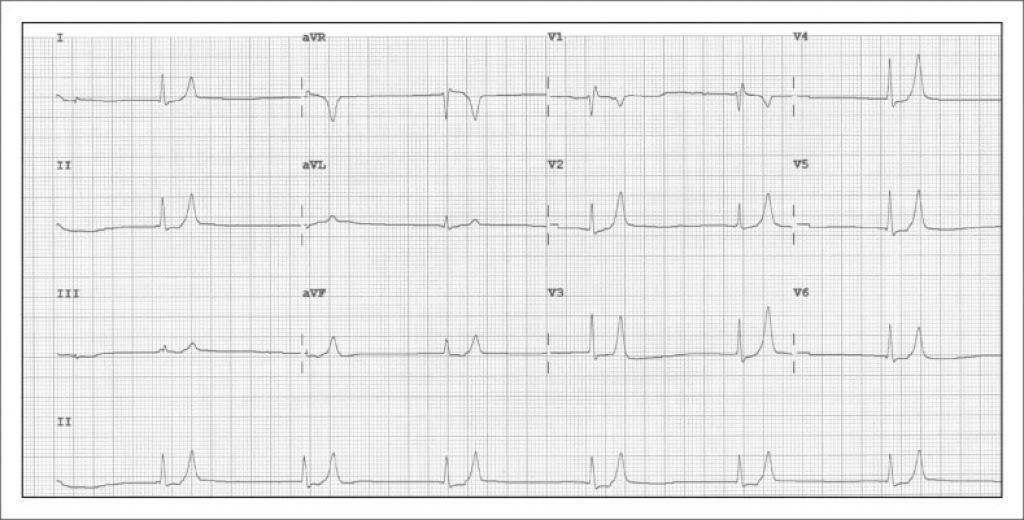

Figura 2: ECG de 12 derivações (25mm/seg e 10mm/mV) evidenciando taquicardia de complexo largo (QRS 240ms) e padrão sinusoidal. Hipercalemia grave com potássio sérico de 9,9mmol/L.